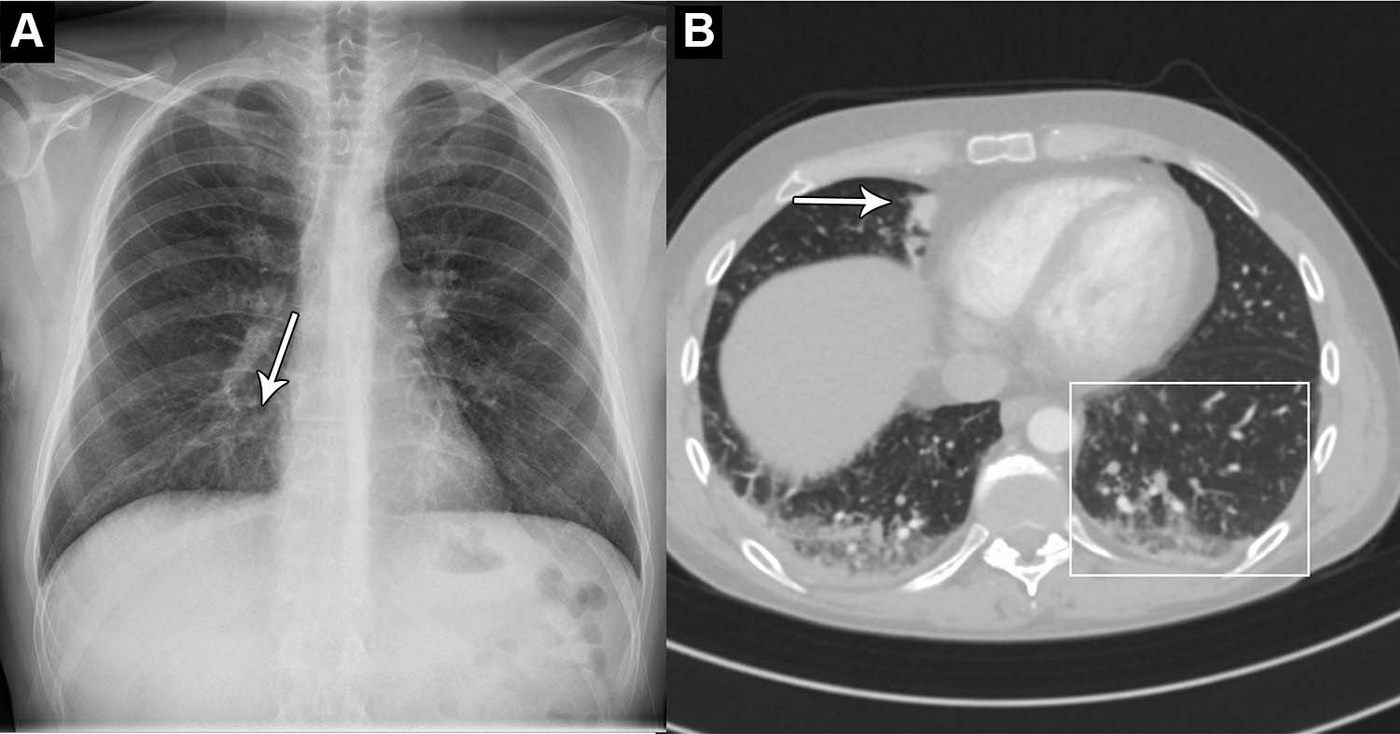

An abnormal chest X-ray can be an indication of a range of conditions, including cancer and chronic lung diseases.

The AI tool identified abnormal chest X-rays with a 99.1% sensitivity rate, which included those with critical, remarkable, and unremarkable abnormalities. In 10 cases there were false negatives, 9 of which were clinically insignificant. The significant one, a subtle lesion, was also missed by one of the attending radiologists.